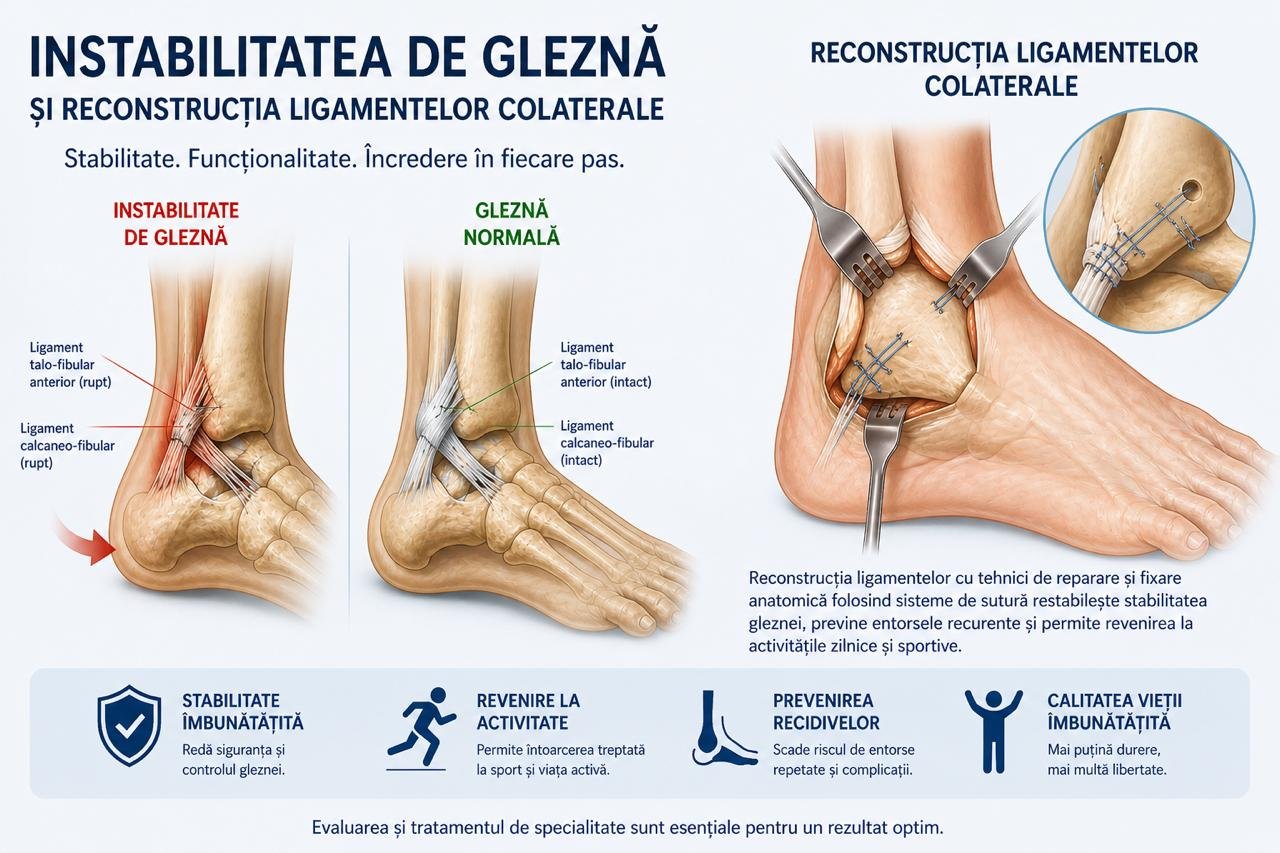

- Instabilitatea Gleznei și Reconstrucția Ligamentelor Laterale